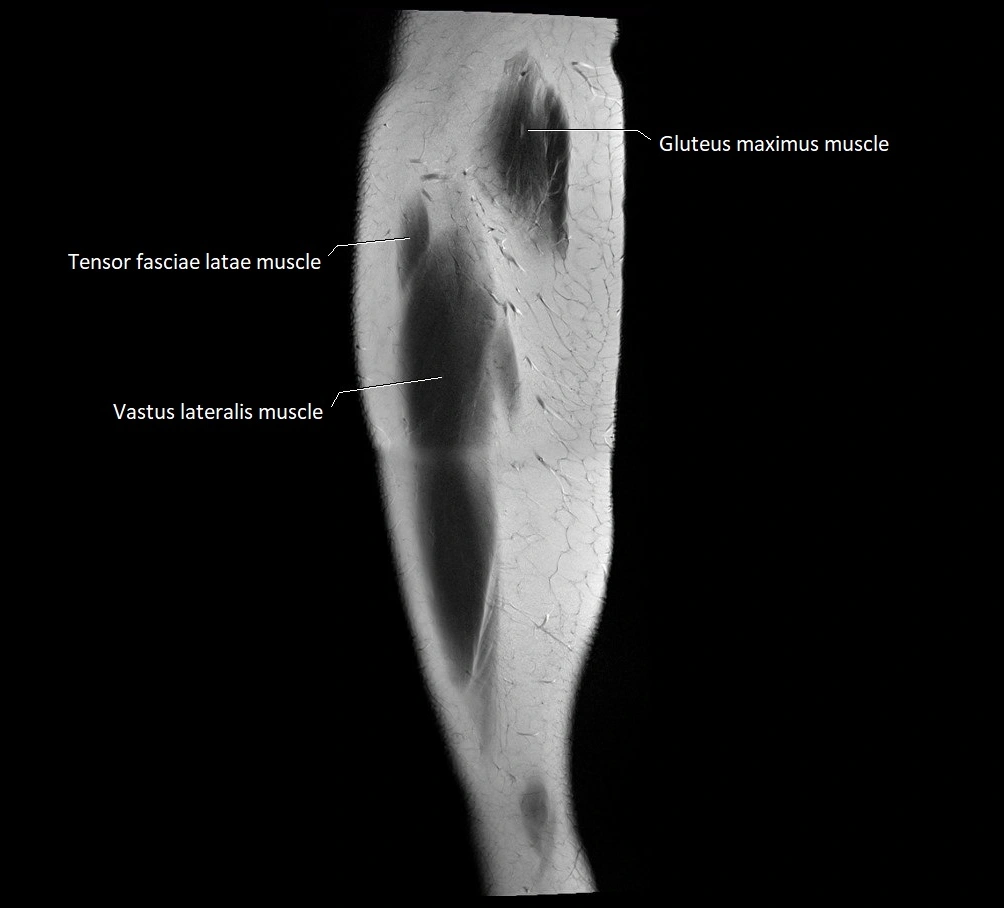

- Gluteus maximus muscle

- Tensor fasciae latae muscle

- Vastus lateralis muscle